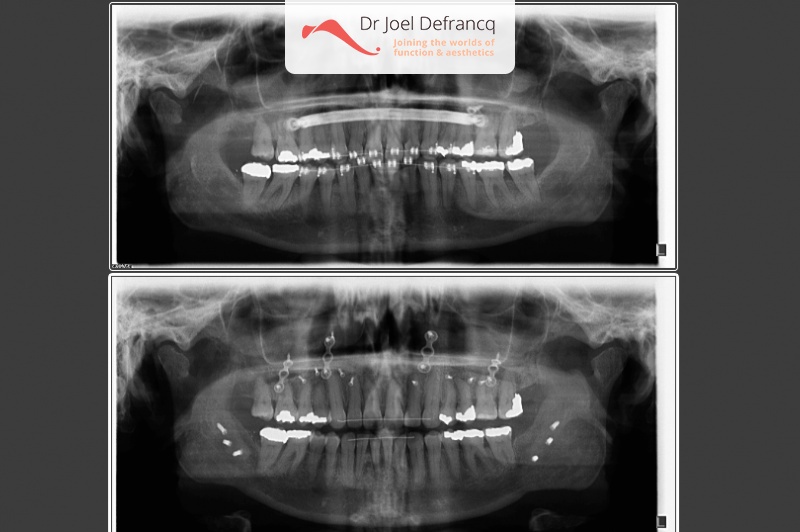

Kaakchirurgie

- Verlenging onderkaak (BSSO)

- Vertikale verlenging bovenkaak (Le Fort I)

- Verbreden bovenkaak (Smile distractor)